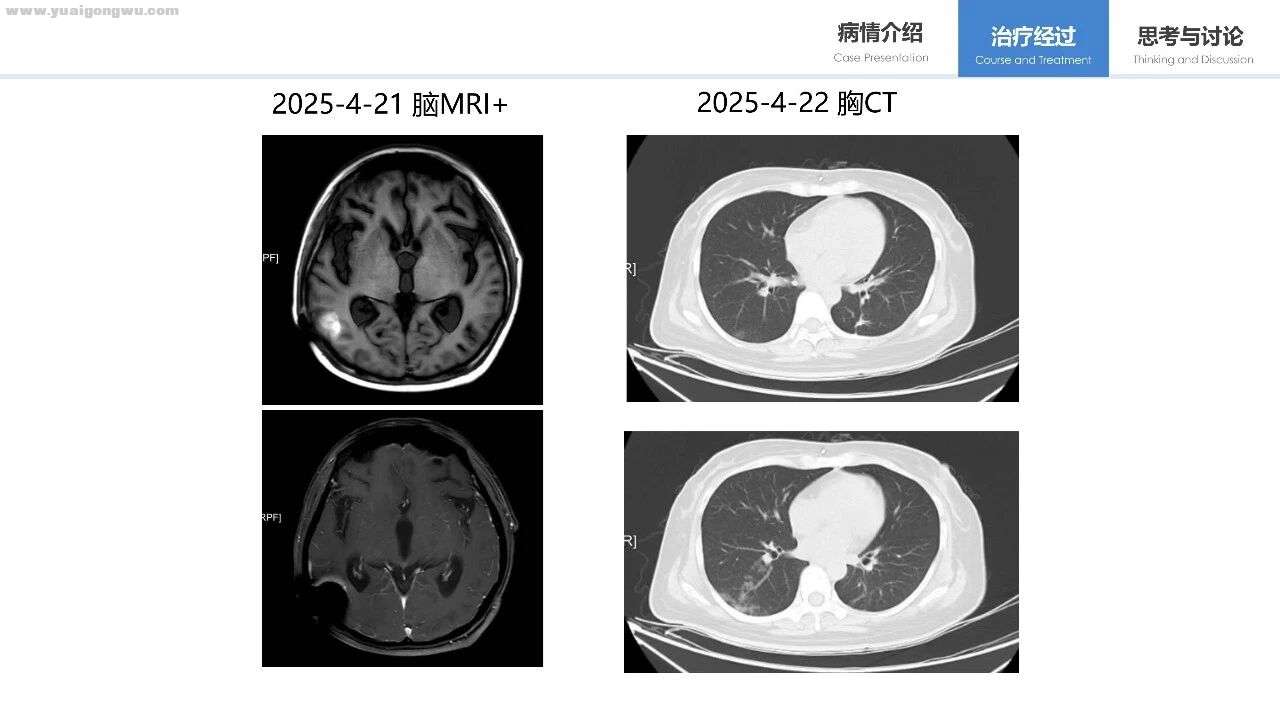

图像显示,上方T1平扫与下方T1增强图像均未显示明显病灶。由于目前提供的层面过少,左侧枕叶的异常信号更可能是置泵产生的伪影(下方伪影更为显著)。值得注意的是,患者脑室较初诊时已有增宽表现。尽管患者以头痛(疑为脑膜转移相关症状)为主诉,且该症状可能影响其活动,但如需准确定位脑膜病变位置,建议提供电子版序列图像进行逐层分析,当前仅有的两层图像除置泵伪影及脑室增宽外,暂未发现其他特征。

吕岩教授 第三位患者的影像资料较前两位更为完善。其主要病情为右下肺病灶伴全身多发转移(含骨转移),经治疗后部分全身病灶缓解,部分仍有进展,与头颅核磁所示病灶变化的时间节点大致吻合。当前头颅核磁显示,右顶叶存在典型转移灶,病灶体积较前增大,红圈标记区域可见病灶周围水肿,其余脑部区域因未提供影像资料,暂无法评估。